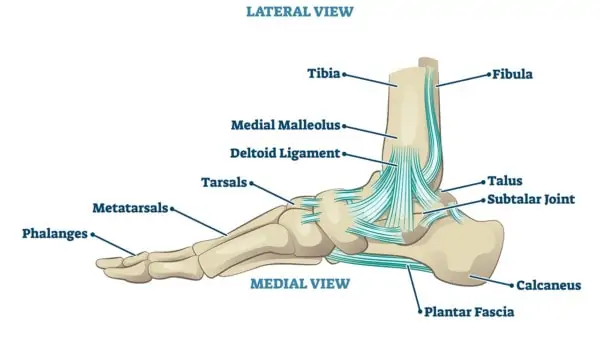

what are the bones of the lower leg?

tibia

fibula

which contains the medial malleoli?

tibia

which contains the lateral malleoli?

fibula, it is longer and projects further than medial

what are the tarsal bones?

cuneiforms

cuboid

navicular

calcaneus

talus

what are the bones of the foot?

metatarsals

phalanges

what are the joints of the ankle complex?

distal tibiofibular joint

talocrural joint

subtalar joint

what are the medial ligaments of the deltoid ligament?

anterior tibiotalar

tibionavicular

tibiocalcaneal

posterior tibiotalar

what is the deltoid ligament?

what does the deltoid ligament do?

restrict eversion

what is plantar fascia?

plantar aponeurosis

plantar fascia

O: medial tubercle of calcaneus

what does the plantar fascia look like?

will band out and bands out to base of toes